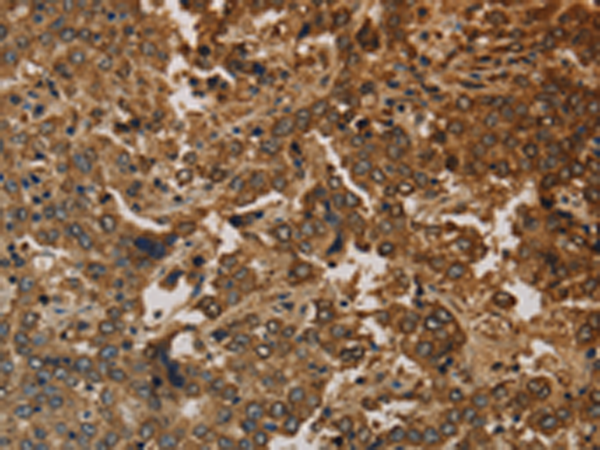

分类: 科研抗体货号: P10761别名: KACL; PILAR; UNQ5792应用: IHC反应种属: Human